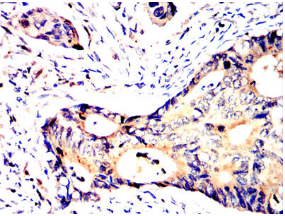

SV2C Mouse Monoclonal antibody[5G11D]

SV2C (Synaptic Vesicle Glycoprotein 2C) is a Protein Coding gene. Diseases associated with SV2C include Foodborne Botulism and Alcohol-Related Birth Defect. Among its related pathways are Toxicity of botulinum toxin type F (BoNT/F) and Uptake and actions of bacterial toxins. Gene Ontology (GO) annotations related to this gene include transporter activity and transmembrane transporter activity. An important paralog of this gene is SV2A.

Species Reactivity:    Human

Immunogen:    Purified recombinant fragment of human SV2C (AA: extra mix) expressed in E. Coli.

IHC    1/200 - 1/1000